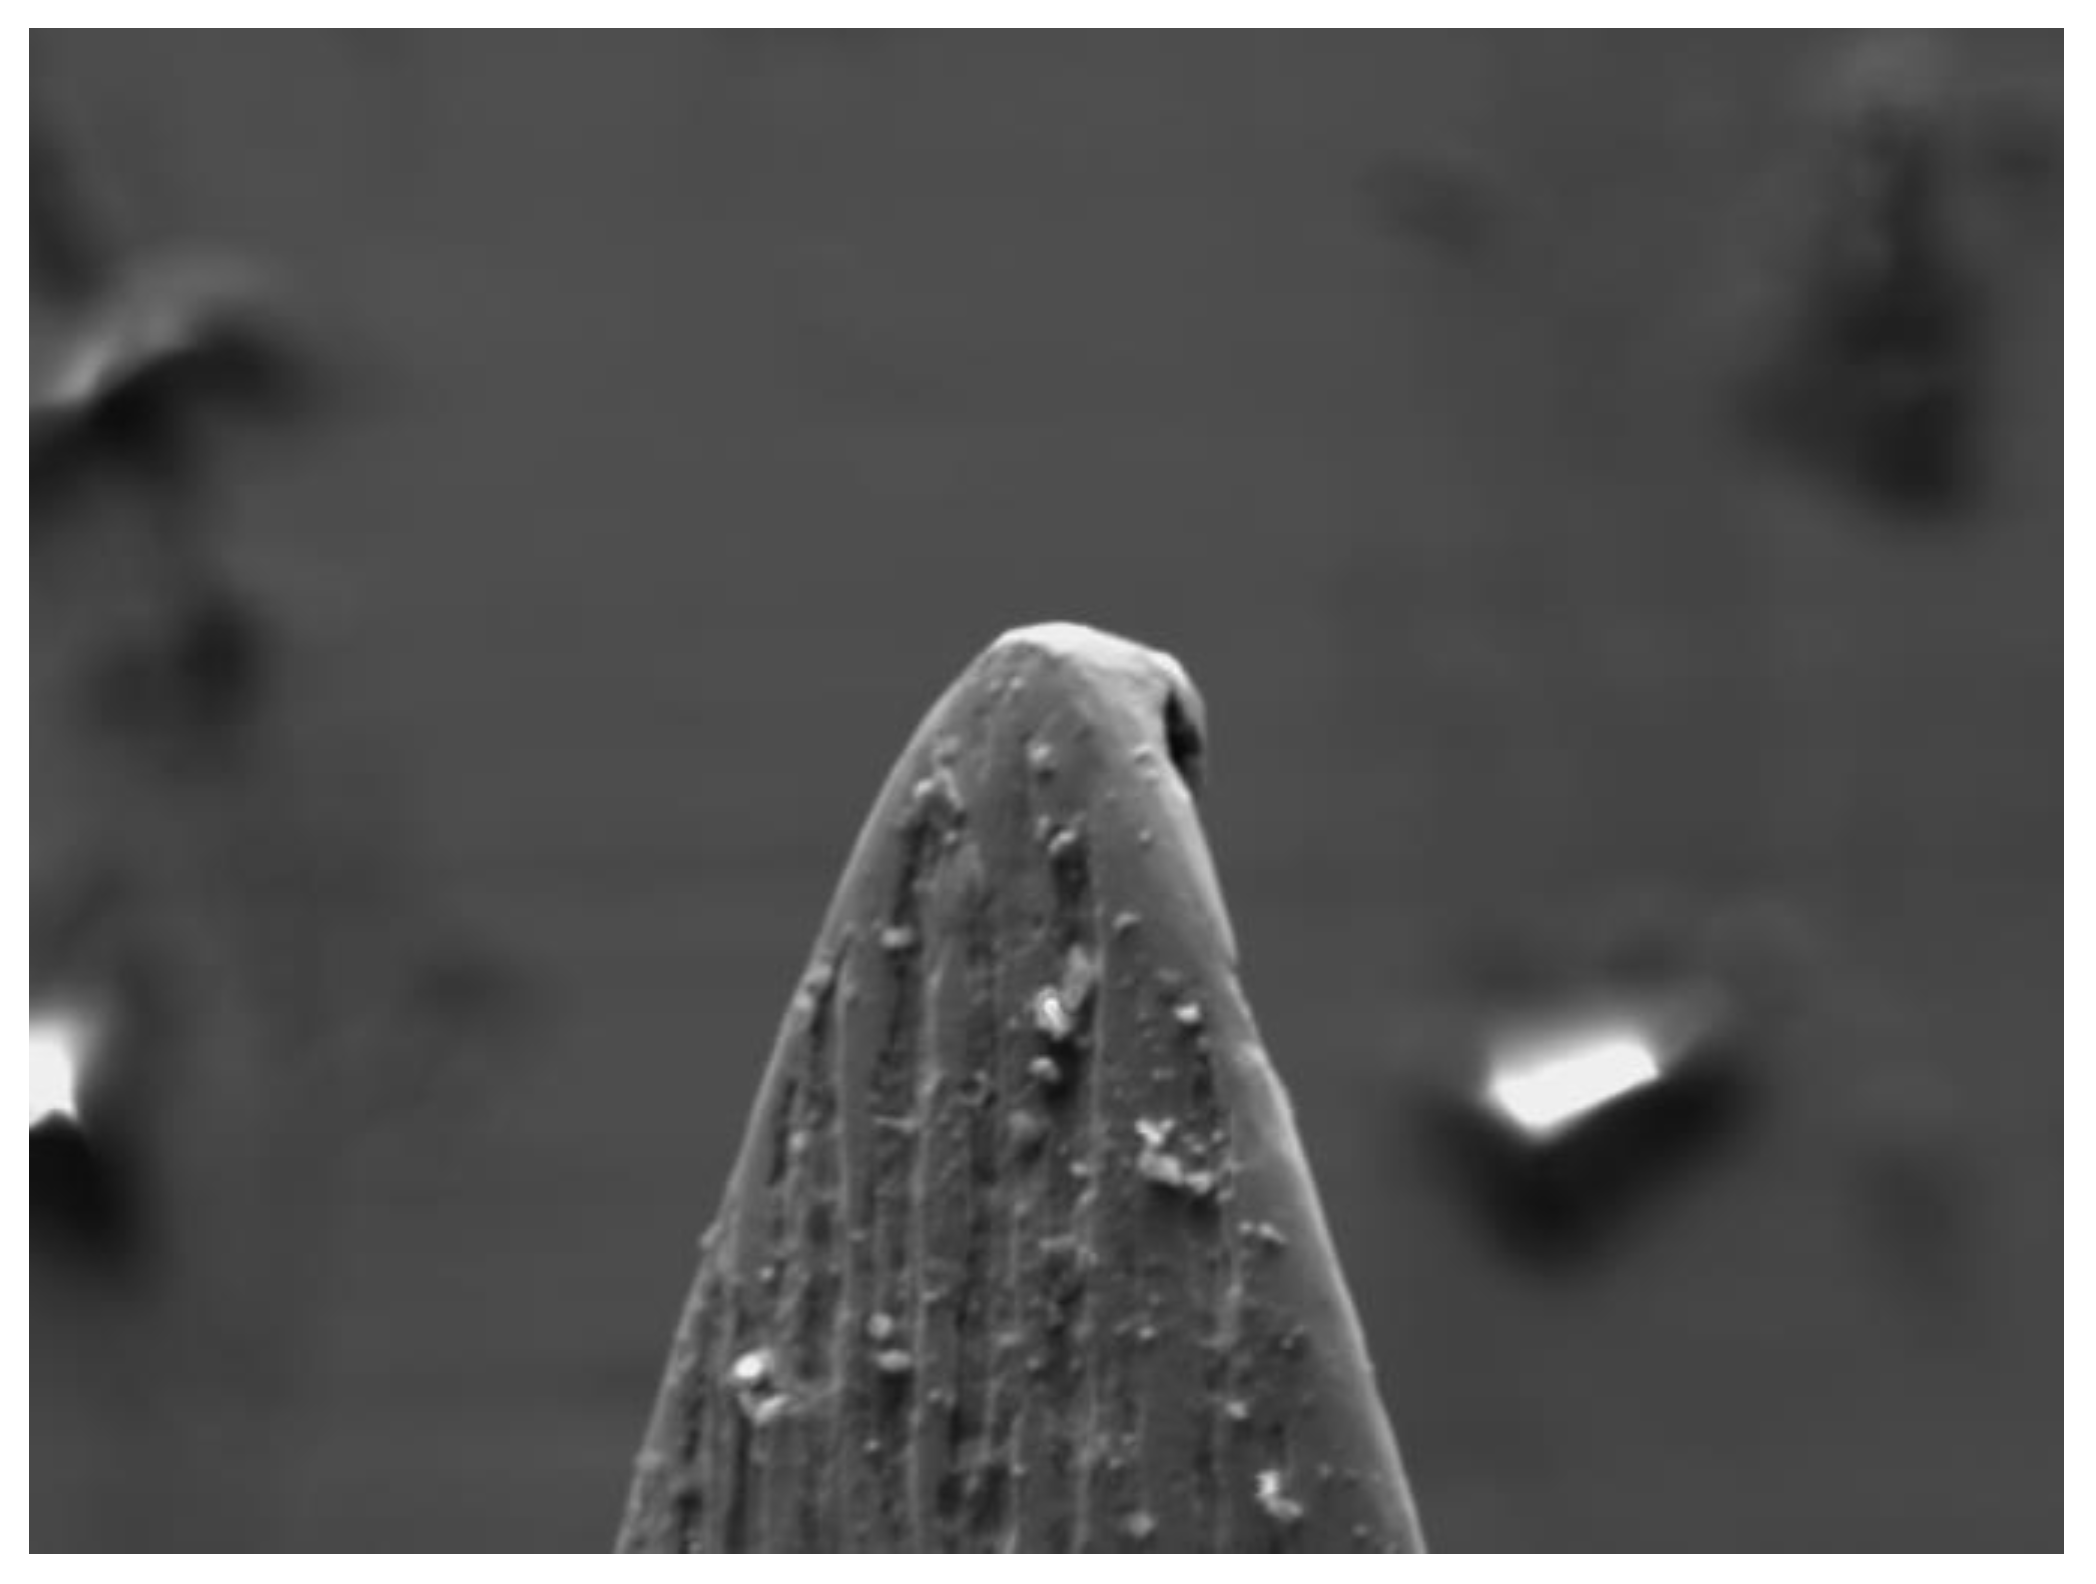

The SEM observation also allowed us to precisely measure some dimensional values ​​of the tested needles to evaluate the homogeneity of the construction dimensional parameters and any differences between groups A and B; in order to carry out this measurement the needles were observed from different observation points. (Figure 4 and Figure 5).

All needles (30G) tested and observed under SEM showed an external diameter of 0.30 mm (+/- 0.03) and an internal diameter of 0.15 mm (+/- 0.04).

Figure 4. Initial measurement of new needles.

Preprints 111024 g004

Figure 5. Measurement of wall thicknesses.

Preprints 111024 g005